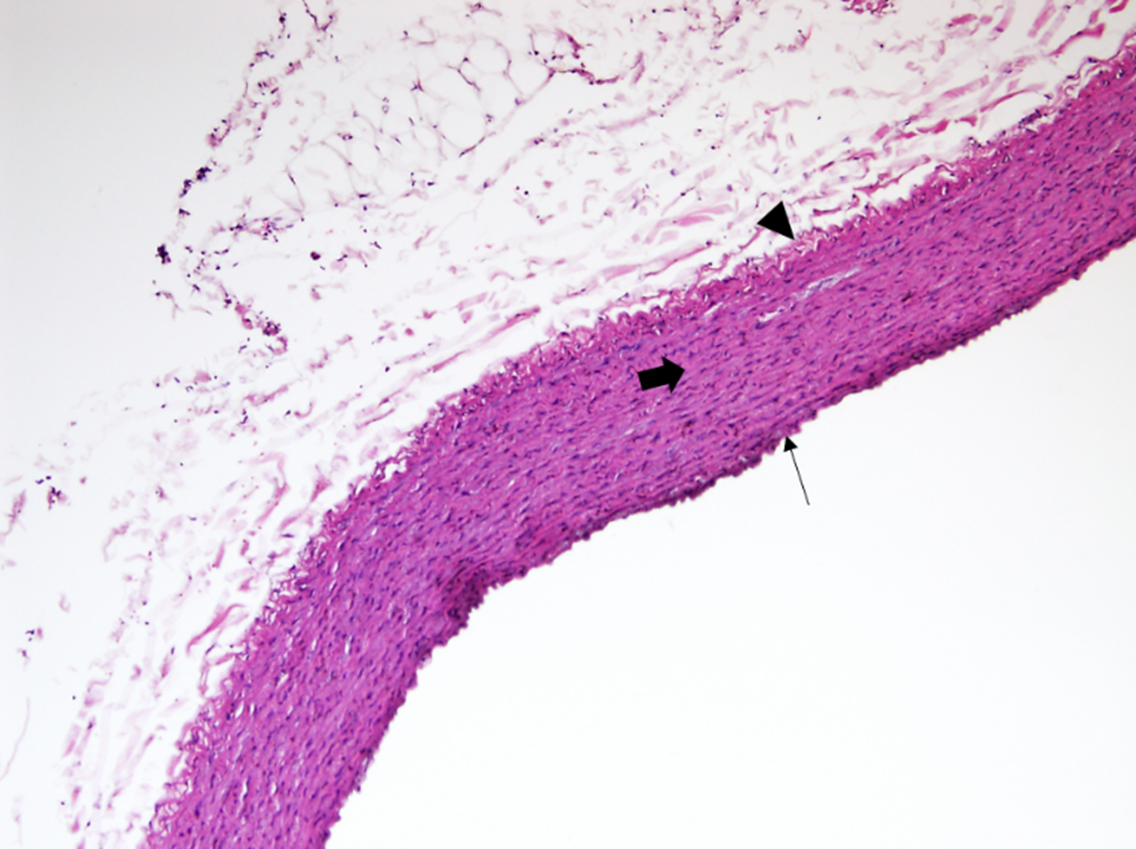

The histological examination of aorta in group A, the control group showed intact tunica intima with thin wavy corrugated endothelium, a normal subendothelial layer, and wavy internal elastic fibers. The tunica media is comprised of elastic fibers and smooth muscle. The outermost layer is the tunica adventitia and is made up of loose connective tissue (Figs. 7,8). In group B, the tunica intima showed the presence of focal thickening, filled with vacuolated cells or foam cells, resulting in the widening of the subendothelial layer (Fig. 9). The tunica intima of the aorta in group C showed intimal thickening with subendothelial collection of foam cells as well as formation of a lipid core and fibrous cap (Fig. 10).

Fig. 8.A photomicrograph in a section of aorta in group A stained by

hematoxylin and eosin (40